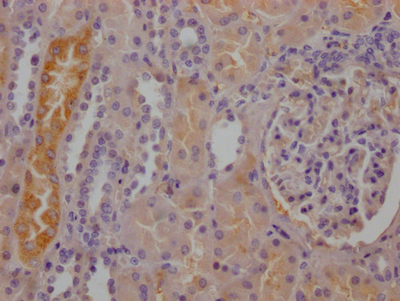

IHC image of CSB-RA784971A0HU diluted at 1:100 and staining in paraffin-embedded human kidney tissue performed on a Leica BondTM system. After dewaxing and hydration, antigen retrieval was mediated by high pressure in a citrate buffer (pH 6.0). Section was blocked with 10% normal goat serum 30min at RT. Then primary antibody (1% BSA) was incubated at 4°C overnight. The primary is detected by a Goat anti-rabbit IgG polymer labeled by HRP and visualized using 0.05% DAB.